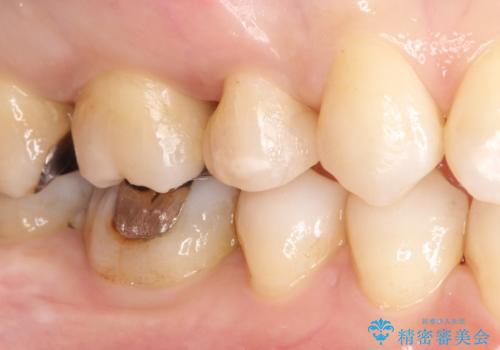

笑ったら銀歯が見える。 セラミックインレーによる治療

- 笑ったときに銀の詰め物が見えることを主訴に来院されました。

セラミックインレーにて修復を行いました。